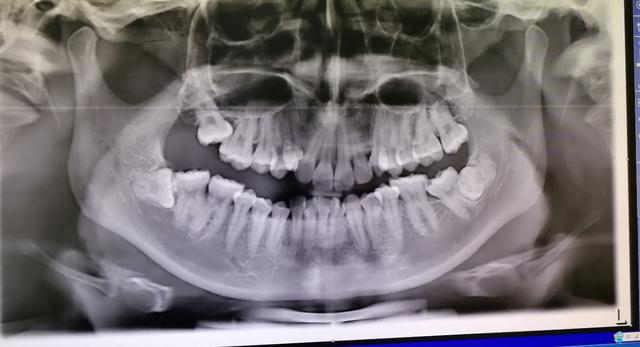

他智点牙根很长,离下牙槽神经很近,我给他拍过口腔ct发现,牙根和神经管之间有一点重叠,牙根与神经管之间没有骨质阻挡,于是我建议他做截冠助萌,等牙齿根离开神经管远一点以后再拔牙齿,这样分两次处理虽然麻烦一点,但是很安全

(绿色箭头指的是下牙槽神经管,黄色箭头指的是牙根,两者有重叠,须加拍cT)